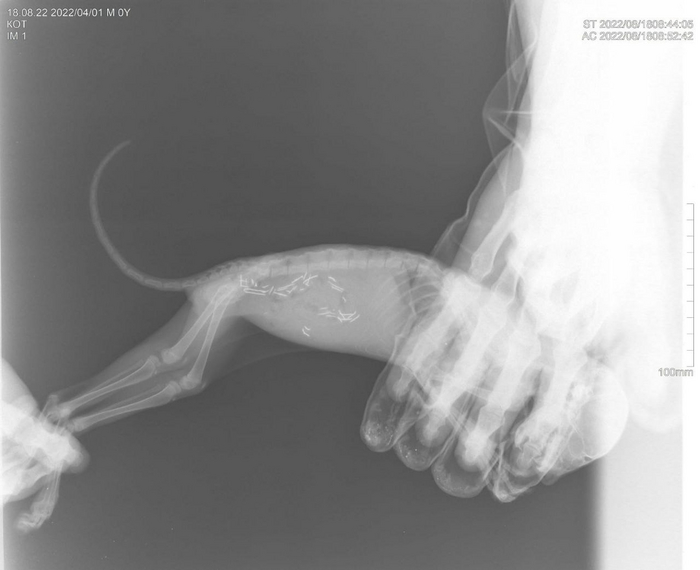

Напомним, что один из выпускников, это котик, у которого при поступлении были обнаружены гвозди в кишечнике. К счастью, обошлось без операции и без последствий для здоровья животного.